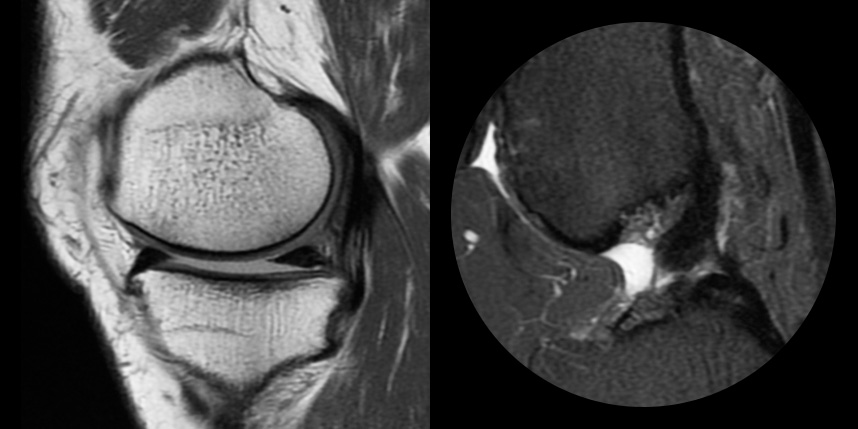

손상된 관절 연골을 재생시켜 관절 기능을 회복하고 통증을 완화하는 치료법입니다.

다양한 연골재생술 기법이 있으며, 환자의 상태와 손상 정도에 따라 적절한 방법을 선택합니다.

연골손상의 단계를 결정할 때 사용하는 ICRS 단계에서 3단계 미만의 연골손상에 사용하는 방법으로 울퉁불퉁한 표면을 다듬어 주는 정도의 수술법입니다.

4단계 이상일 경우 미세천공술을 기본으로 시행하며, 미세천공술로 나온 본인의 골수줄기세포와 함께

연골 생성을 촉진할 수 있는 “재료”를 같이 주입하는 치료를 시행합니다.

손상된 연골 부위에 작은 구멍을 뚫어 골수에서 나오는 줄기세포를 이용하여 연골 재생을 유도하는 방법으로 근본적으로 섬유연골(정상연골보다는 약한 연골)로 재생된다고 알려져 있습니다.